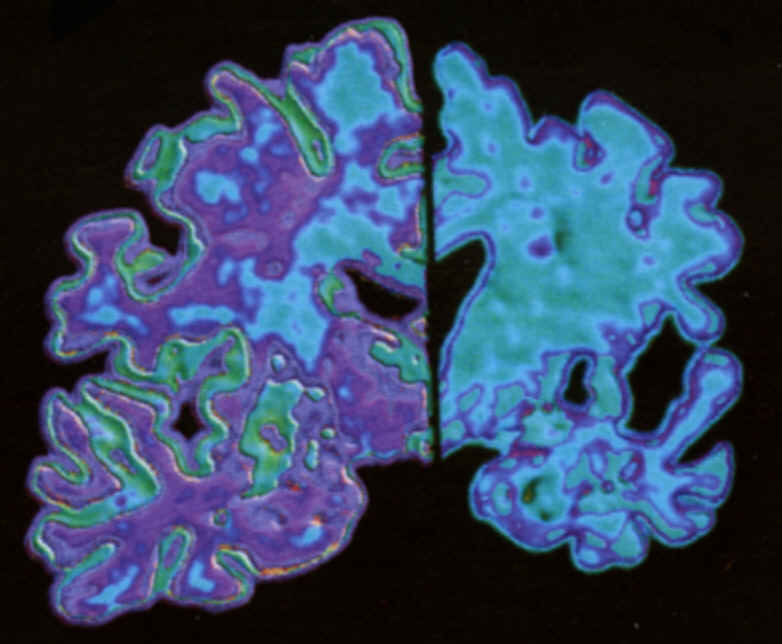

Hoy se celebra el Día Mundial del Alzheimer (21 de septiembre), desde esta entidad tenemos previsto realizar las siguientes actividades:

Hoy se celebra el Día Mundial del Alzheimer (21 de septiembre), desde esta entidad tenemos previsto realizar las siguientes actividades: